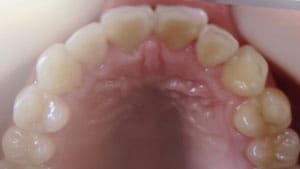

● 先天性の萌出方向異常を部分矯正で治療

藤沢デンタルオフィスの虫歯や破折で先天性の萌出方向異常を部分矯正で治療

01

02

03

04

05

06